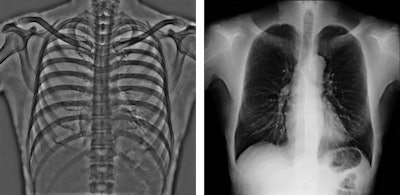

Tomosynthesis image of an ankle taken with Shimadzu's RADspeed Pro digital radiography system.The emphasis of Philips' researchers has been on developing technologies for improving diagnostic quality while eliminating inefficiencies when using mobile digital radiography systems at the patient's bedside. The new SkyFlow scatter correction algorithm reduces the effect of scattered radiation for nongrid bedside chest exams, allowing the operator to obtain DR images with grid-like contrast, but avoiding the time and effort involved in attaching and detaching a grid.

Pelvic radiographs taken with and without SkyFlow scatter suppression algorithm. Image courtesy of Philips.

Chest radiographs taken with SkyFlow scatter suppression algorithm and standard acquisition. Image courtesy of PhilipsOn the GE Healthcare stand, its representatives are keen to discuss new evidence showing the clinical value of its long established digital tomosynthesis technology, VolumeRAD. A recently completed international multicenter clinical trial has demonstrated that the product offers improved detection and management of patients with lung nodules compared with conventional radiography – with a 7.5 times increase in sensitivity for nodules between 4 mm and 6 mm diameter compared with standard x-ray. The device is reportedly 3.6 times more sensitive than conventional two-view computed radiography, without decreased specificity of detection of small lung nodules in the range of 3 mm to 20 mm in diameter.